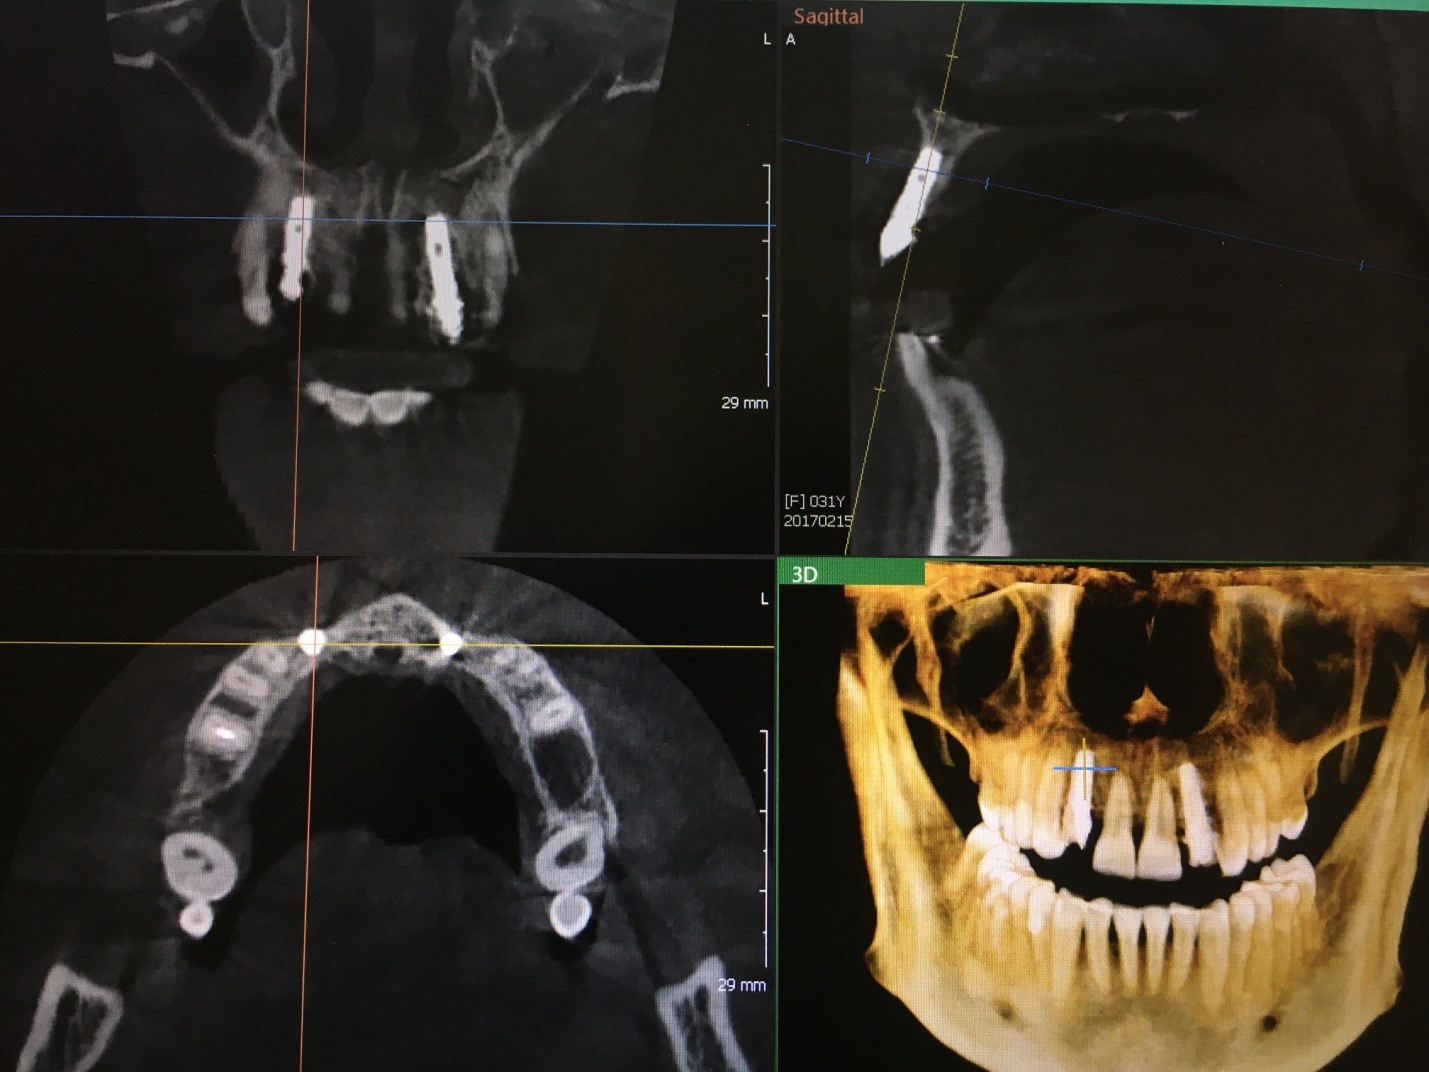

Рис. 1 Дентальная объемная томограмма после проведения одномоментной имплантации в проекции 31,41 зубов. Инклинация имплантатов корректна